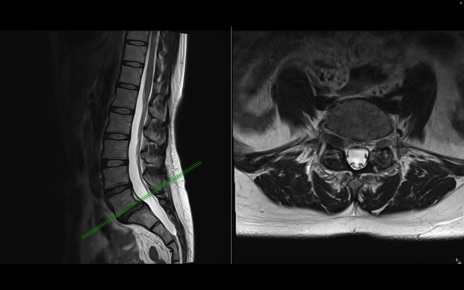

腰椎MRI

T2WI(横断像)

T2WI(矢状断像)